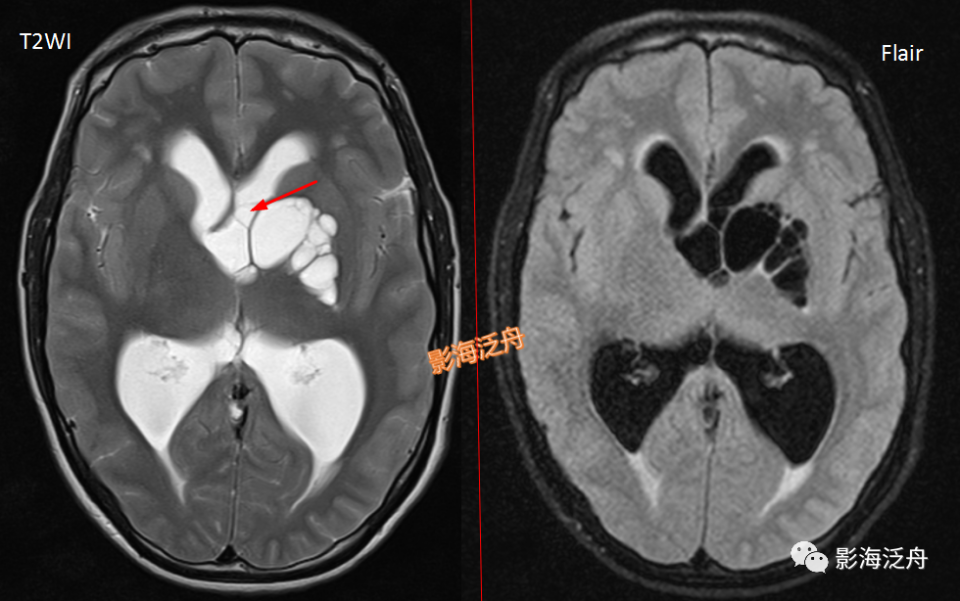

左侧基底节区腔梗灶,病灶既不像类圆形也不像规则的长条状,在Flair序列上灶周可以看到淡淡的高信号影(红箭)。基底节区的腔梗灶位置相较于扩大VR腔隙往往更加靠近上份层面、形态不规则,且随着病程时间延长Flair序列高信号会愈加明显。

图片

左侧基底节区腔梗灶(红箭头),尽管后部的那个病灶看起来有点圆,但在Flair序列病灶周围可以看到非常明显的高信号(绿箭),代表局部胶质增生,证明其为慢性期腔梗灶而非扩大的VR腔隙,其余病变(黄箭)为对称性分布,呈斑点状或长条状,Flair序列灶周无高信号,诊断VR腔隙更为合理。